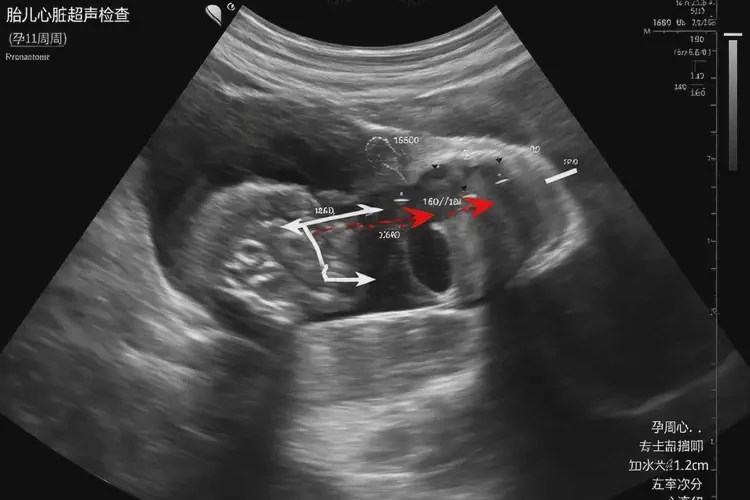

胎心率79次/分鐘 在孕11周3天的情況下明顯偏低。正常情況下,孕11周左右的胎心率應(yīng)在120-160次/分鐘之間。胎心率低于120次/分鐘可能提示胎兒宮內(nèi)窘迫或其他潛在問題。

胎心率是評估胎兒健康狀況的重要指標之一。在孕早期,胎心率通常較快,隨著孕周增加會逐漸穩(wěn)定。在孕11周3天時,胎心率僅為79次/分鐘,這可能引起擔(dān)憂。以下是可能的原因和相關(guān)信息:

孕11周3天胎心率79怎么回事(圖1)